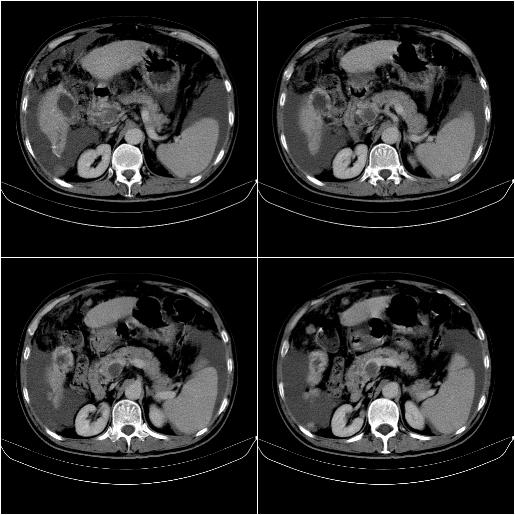

标题: CT21651:M,67Y,肝癌9月,介入术后3月。

m,67y,肝癌9月,介入术后3月。现腹胀、纳差、腹泻。

1)肝癌介入治疗术后碘油沉积不良。2)门静脉瘤栓形成,腹膜广泛性转移。3)肝硬化,脾大,腹水。4)慢性胆囊炎。